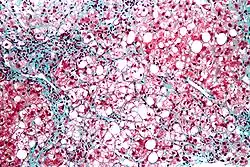

Micrograph showing a fatty liver (macrovesicular steatosis), as seen in metabolic dysfunction–associated steatotic liver disease. Trichrome stain.

The fatty change represents the intracytoplasmatic accumulation of triglycerides (neutral fats). At the beginning, the hepatocytes present small fat vacuoles (liposomes) around the nucleus (microvesicular fatty change). In this stage, liver cells are filled with multiple fat droplets that do not displace the centrally located nucleus. In the late stages, the size of the vacuoles increases, pushing the nucleus to the periphery of the cell, giving a characteristic signet ring appearance (macrovesicular fatty change). These vesicles are well-delineated and optically "empty" because fats dissolve during tissue processing. Large vacuoles may coalesce and produce fatty cysts, which are irreversible lesions. Macrovesicular steatosis is the most common form and is typically associated with alcohol, diabetes, obesity, and corticosteroids. Acute fatty liver of pregnancy and Reye's syndrome are examples of severe liver disease caused by microvesicular fatty change.[19] The diagnosis of steatosis is made when fat in the liver exceeds 5–10% by weight.[13][20][21]